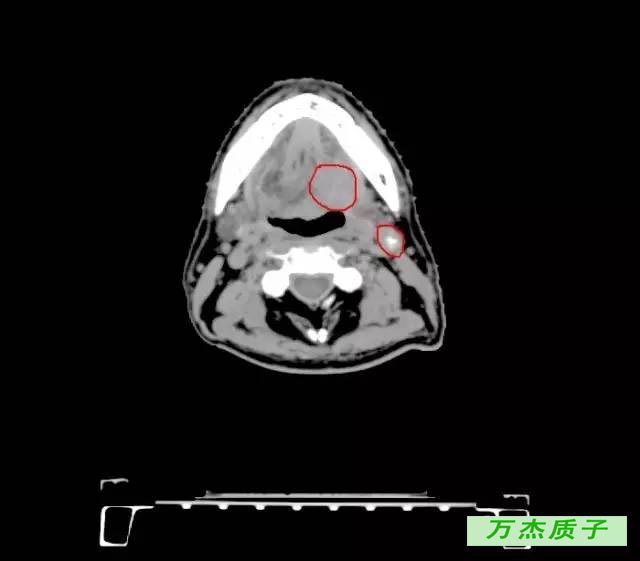

舌癌治愈率是多少 发布时间: 61次浏览 舌癌大家不会陌生,它是口腔颌面部常见的恶性肿瘤,发病率越来越高,严重的危害了我们的健康,有些舌癌患者会担心一个问题,舌癌的治愈率是多少,这关系到患者的人身安全。 舌癌的颈淋巴结转移率为29%~38%,与病程早晚期相关。治疗舌癌,先采用放射治疗而不应急于手术。直径在2厘米以下的治愈率,可高达%。 舌癌治疗 ( 一 ) 舌癌的一般疗法 (1) 舌癌患者因舌痛、舌肿大、溃烂、出血等影响进食 , 进食可以流质和半流质为主。

舌癌临床表现 编辑 播报 1肿瘤多发生于舌缘,其次为舌尖、舌背及舌腹等处,可有局部白斑病史或慢性刺激因素。 2常为溃疡型或浸润型,生长快,疼痛明显,浸润性强。 3可有舌运动受限、进食及 吞咽困难 。 4早期常发生颈淋巴结转移。舌癌诊疗知识 就诊科室: 肿瘤科 口腔科 治疗费用: 不同医院收费标准不一致,市三甲医院约( —— 元) 治愈率: 治疗周期: 治疗方法: 药物、手术治疗舌癌的治愈率有多大? 如果不能彻底治好,大约能活多久? _百度知道 舌癌的治愈率有多大? 如果不能彻底治好,大约能活多久? 首页 在问 全部问题 娱乐休闲